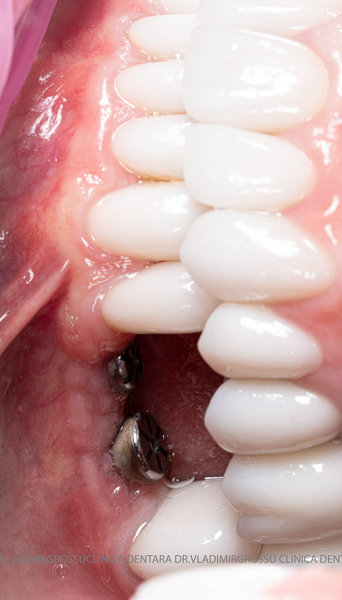

Aditia gingivală este o procedură chirurgicală ce corectează diverse probleme estetice și funcționale, cum ar fi recesiunea gingivală. În implantologia modernă, aditia de țesut moale este utilizată aproape în fiecare intervenție de inserție a implantului dentar pentru a asigura un aspect estetic natural și o bună integrare a implantului în cavitatea bucală.

Adiția osoasă are un rol crucial pentru poziționarea corectă și stabilă a implanturilor dentare. Clinica stomatologică Dr. Grossu din Chișinău promovează o abordare chirurgicală estetică și predictibilă, adaptată fiecărui caz în parte.

Medicii noștri au o vastă experiență atât în chirurgia estetică, cât și în protezarea cu un grad înalt de naturalitate, ceea ce ne permite să gestionăm cu succes și cele mai complexe cazuri.